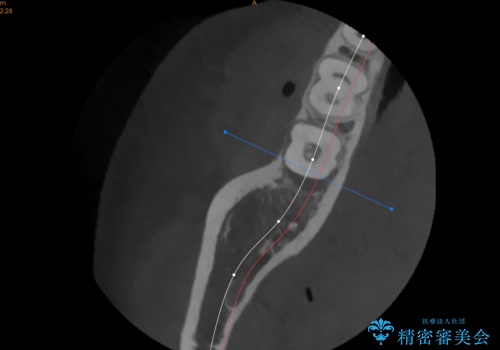

遠心から舌側、唇側に及ぶ深い垂直的骨欠損も認めたため、歯科衛生士による歯周基本治療の後、歯周外科(再生療法)を行いました。

レントゲン写真は、処置後一年経過時のもので、歯周ポケットは遠心4mm、舌側3mmまで減少、出血なし。

一度目の再生療法でできる骨形態は移行的でないこともあるため、経過を診つつ骨整形も必要であれば今後行う予定です。